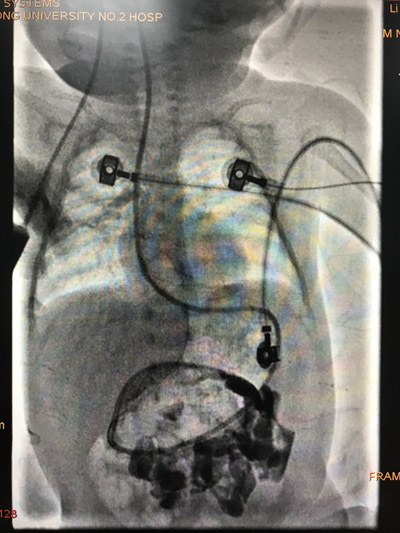

近日小儿外科收治一例外院先天性食道闭锁术后吻合口漏的患儿,因无法正常进食或早期肠内营养,需行暂时性胃造口术。李鹏主任医师经详细询问病史及查体后,考虑患儿目前情况,为避免再次手术给患儿及其家庭带来巨大痛苦,和家长充分沟通后决定行DSA介入引导下放置鼻空肠营养管。因此类手术实施对于儿科的护理工作难度很大,经积极充分的术前准备后,于近日在小儿外科曹萍护士长、潘伟康副主任医师、影像科刘强副主任医师充分配合下顺利完成。目前患儿经治疗后已能经管行肠内营养,避免了再次手术,体重增加,恢复顺利拟近日出院。

鼻空肠营养管的早期放置可迅速的建立肠内营养通道,维持肠黏膜屏障功能,避免了再次手术打击及肠道菌群移位。因儿科的护理工作具有其特殊性,小儿不能配合护士操作,需要麻醉镇静下完成。DSA介入引导置入操作,能够实时动态观察放置过程及位置,对小儿食管、胃的损伤明显小于胃镜下放置,另具有不需要麻醉而且降低治疗平均花费等优点。DSA下放置小儿鼻空肠营养管的成功开展,填补了我院小儿护理工作该类术式的空白,达到国内先进水平。